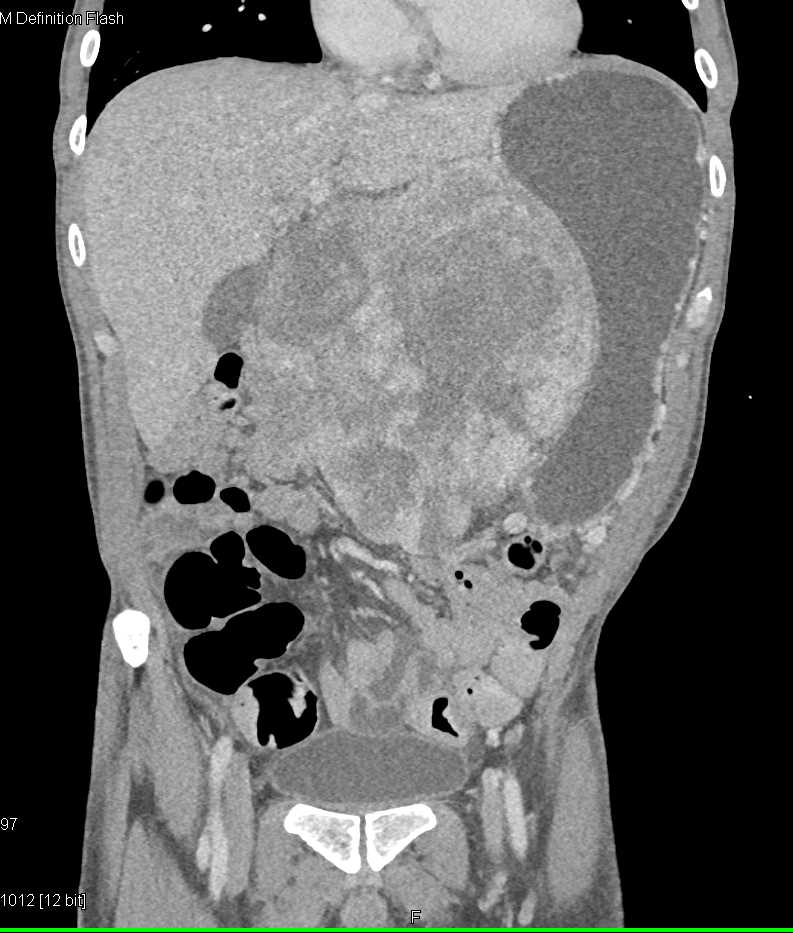

Lagre Gastric GIST Tumor